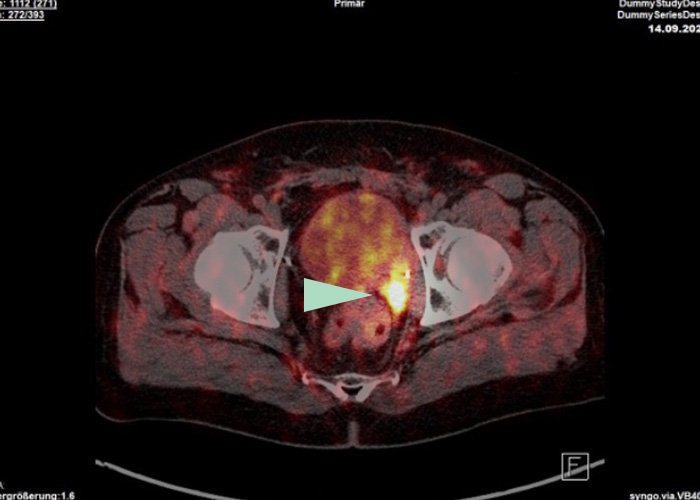

Prostatakrebs

Nachweis eines bisher unerkannten Tumorherdes (s. gelber Pfeil) durch das Fluor-18 PSMA PET-CT links hinter der Harnblase. Die Prostata war mehrere Jahre zuvor operativ entfernt worden. Ein PSA-Anstieg war der Anlass für die Durchführung des PET-CTs.

Mit dem F-18 PSMA PET-CT lassen sich kleine und kleinste Tumorherde und Absiedlungen des Prostatakarzinoms (Metastasen) in Lymphknoten und Organen nachweisen. Auch in der Prostata selbst oder in der Prostataloge wird Tumorgewebe sehr empfindlich detektiert.

Kleinste Tumorherde werden entdeckt (bessere Auflösung)

Tochtergeschwülste (Metastasen) im kleinen Becken und Tumore in der Prostataloge werden zuverlässig gefunden (da keine störende Anreicherung in der Harnblase erfolgt)